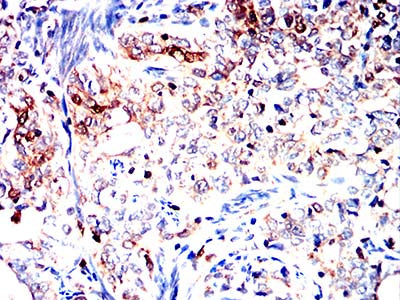

分类: 科研抗体货号: 32392别名: HCC5; P1.h; RLFB; P1-MCM3应用: WB,IHC,IF,FCM反应种属: Human,Rat,Monkey